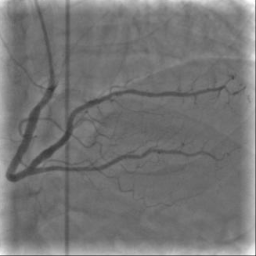

X-ray angiography is the most used imaging modality to visualise blood vessels for interventional purposes such as stenting of stenosed vessels or for diagnostic purposes such as assessment of myocardial perfusion or stenosis grading. To minimise ionising radiation exposure of the patient and medical personnel during image acquisition, low power X-Rays are used resulting in noisy and low contrast images. In the context of diagnosis, the main object of interest is the vascular tree, its branchings and variations in thickness. It is therefore necessary to accurately highlight the vessels in consecutive frames to reduce the noise and improve contrast. In addition, in interventional procedures, identifying interventional instruments (catheter, wires) is also needed in order to better plan and control their positioning. Efficiently discriminating between instruments and vessels as well as other anatomical structures that may have similar appearance is crucial during the interventions. Figure 1(a-c) shows an example of an angiogram sequence. Note large non-rigid motion between frames as well as the ambiguity between vessels and the catheter. Figure 1(e) shows a frame from a different sequence of the same patient but taken at different scan and angle and (f) shows a different patient. There is a significant difference in vessel as well as catheter locations in all three sequences, which we consider as independent examples. Figure 1(d) shows the ground truth segmentation of the first frame.

The dataset consists of anonymised fluoroscopy X-Rays of 26 different patients. The images were acquired during stent placement using a General Electric Innova 2000 system and stored according to standard medical protocol in DICOM format. In total the dataset includes 36000 frames corresponding to 365 distinct video sequences with an average of 98 frames each. Different sequences of the same patient were taken at different angles and stages of the procedure therefore they differ significantly as shown in Figure 1(c)(e)(f). Each frame is rescaled from to due to memory constraints.